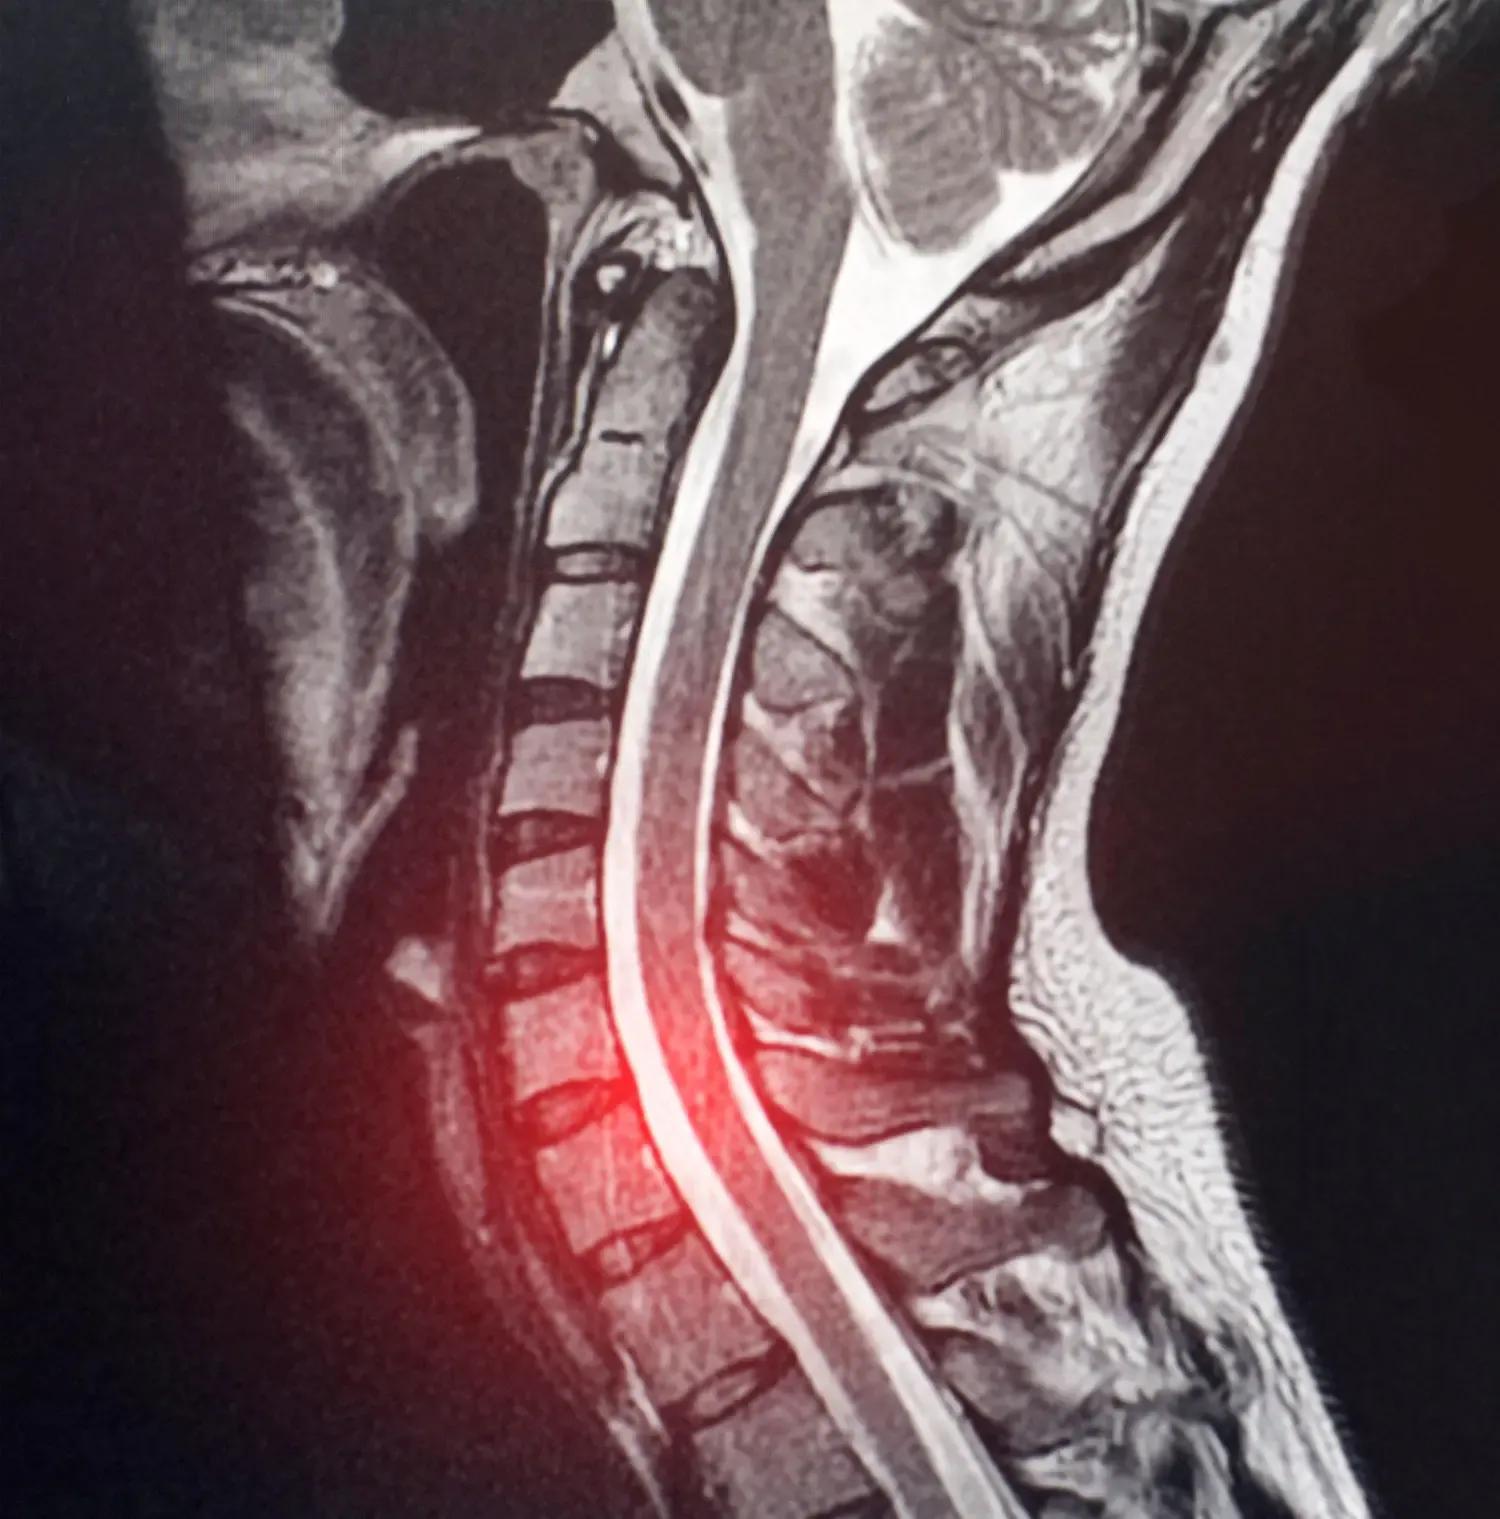

C4-C5 Disc Herniation